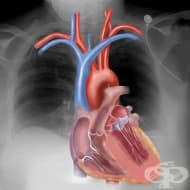

Рентгеновото изследване на гърдите позволява визуализиране на сърцето, белите дробове, дихателните п...